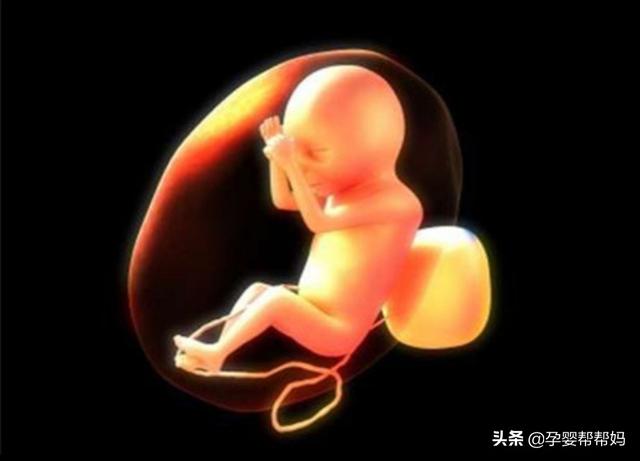

怀孕32周,已经8个月了,虽然胎儿还没有足月,但是如果出生以后护理的好,已经具备了可以存活下去的条件。

一、生长数据:怀孕32周的胎儿:①双顶径在8.17±0.65cm,②股骨长在6.42±0.5cm,③从头到屁股的长度大概在40cm左右。④胎儿体重在1.7千克左右。

二、胎儿状态:孕32周的胎儿皮肤为深红色,脚趾甲已经全部长齐,但是头发还在继续生长(眉毛胎毛已经存在)。虽然孕32周的胎儿还没有足月(37周足月),但是此时胎儿的内脏发育的已经逐渐接近成熟,胎儿的肺部和胃部也接近成熟,已经具备了出生以后呼吸的能力。

孕32周,虽然宝宝还没有足月,但基本发育完全,皮肤呈深红色,身长约40厘米,体重3-5斤。基本占据整个子宫。宝宝的生殖器官已经发育,能较为清楚地看出性别,尤其是男宝宝,阴茎明显。女宝宝的生殖器官较为隐蔽,不容易看出。

虽然孕32周宝宝的五官,四肢等都已经发育,但是肺部功能还没有发育完善,要等到至少37周各方面才发育完全,所以孕妈不要迫不及待地想早点卸货,至少要等到37周宝宝足月后再进行剖腹产手术。